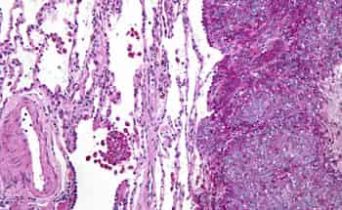

Ricercatori del San Raffaele hanno identificato il meccanismo con cui le cellule tumorali sfuggono al sistema immunitario successivamente all'intervento di trapianto

Ricercatori del San Raffaele hanno identificato il meccanismo con cui le cellule tumorali sfuggono al sistema immunitario successivamente all'intervento di trapianto